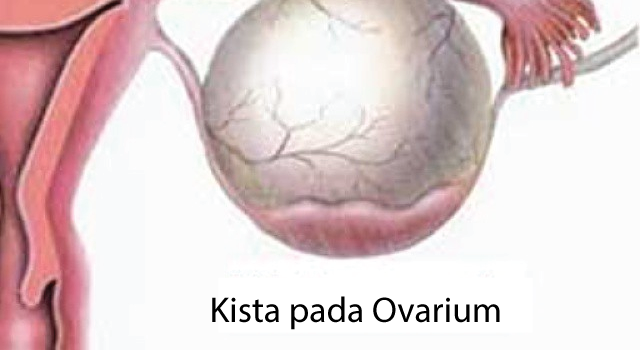

Гистологические изображения фолликулярной кисты яичника